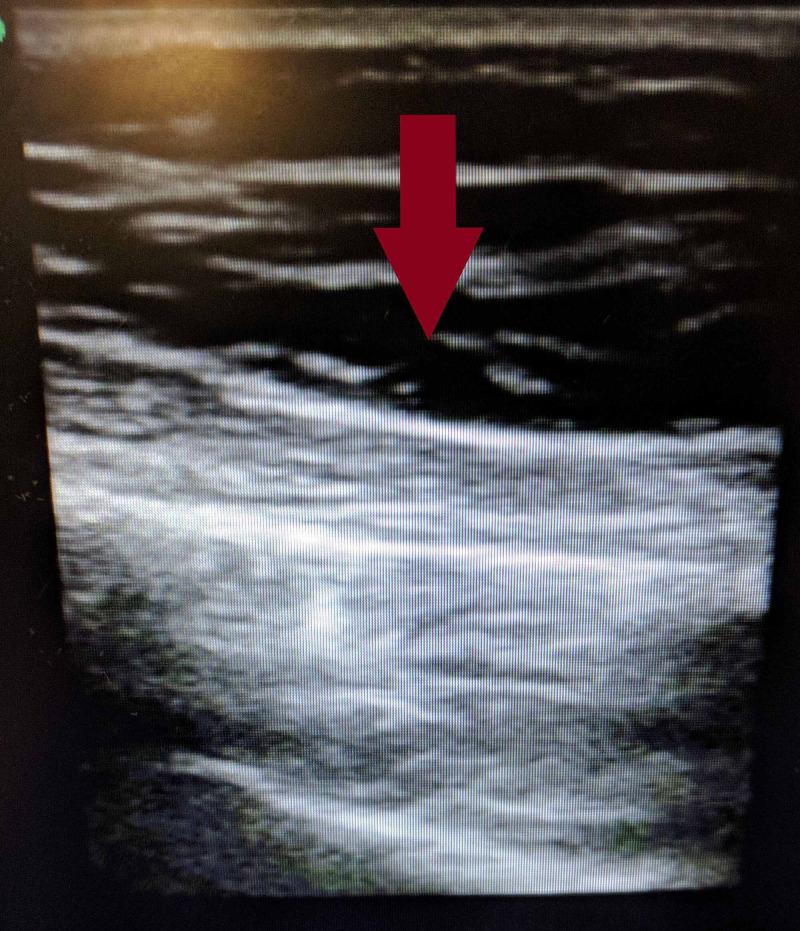

Necrotizing soft tissue infections typically begin with direct inoculation of bacteria into the subcutaneous tissues. Here, we present a case with no such exposure, but with severe necrotizing fasciitis. We present a middle-aged man presented to the emergency department for a presumed allergic reaction after having initially sought care twice at an urgent care facility. The patient had swelling, but no tenderness of his right lateral chest and flank. Subsequent imaging showed extensive fluid in the fascial planes of the right chest wall requiring surgical debridement. Necrotizing fasciitis that is not treated with surgical debridement carries a mortality rate approaching 100%. This case highlights a potential atypical presentation as well as highlights the fact that the Laboratory Risk Indicator for Necrotizing Fasciitis (LRINEC) score lacks sensitivity to rule out a necrotizing soft tissue infection, requiring surgical debridement for diagnosis.

摘要

坏死性软组织感染通常始于细菌直接接种到皮下组织。在此,我们报告一例没有此类暴露史,但患有严重坏死性筋膜炎的病例。我们介绍一名中年男性,他最初在紧急护理机构就诊两次后,因疑似过敏反应而被送往急诊科。患者右侧胸壁和侧腹肿胀,但无压痛。随后的影像学检查显示右胸壁筋膜平面有大量积液,需要手术清创。未经手术清创治疗的坏死性筋膜炎死亡率接近100%。该病例突出了一种潜在的非典型表现,同时也突出了坏死性筋膜炎实验室风险指标(LRINEC)评分在排除坏死性软组织感染方面缺乏敏感性这一事实,需要手术清创来进行诊断。